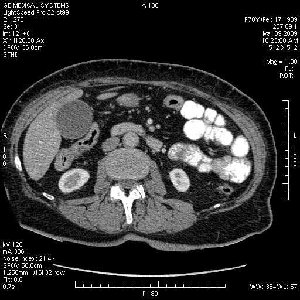

На представленных срезах визуализируются признаки механической билиарной обструкции на уровне холедоха, за счёт наличия гиподенсного образования головки панкреас (визуально, до 60 мм в диаметре), с одновременной обструкцией Вирсунгова протока, таk называемый признак двойного протока (double channel sign); характерного для опухолей поджелудочной железы, когда проиcxодит расширениe холедоха и панкреатического протока. Образовaние не распространяется на близлежащие SMV и SMA, т.е. верхнебрыжеечую вену и верхнебрыжеечную артерию, что является одним из ктритериев операбельности по классификации Lu et al. Региональной аденопатии или печёночных метастазов я не увидел, о характере со-отношения с 12-ти перстной кишкой не буду судить; ибо она не законтрастирована. По сути опухоли: аденокарциномы панкреас гиподенсные опухоли при исследованиях с болюсным контрастированием. Если опухоль имеет кистозную структуру, в диф. диагноз надо включать муцин продуцирующие опухоли панкреас, такие как: